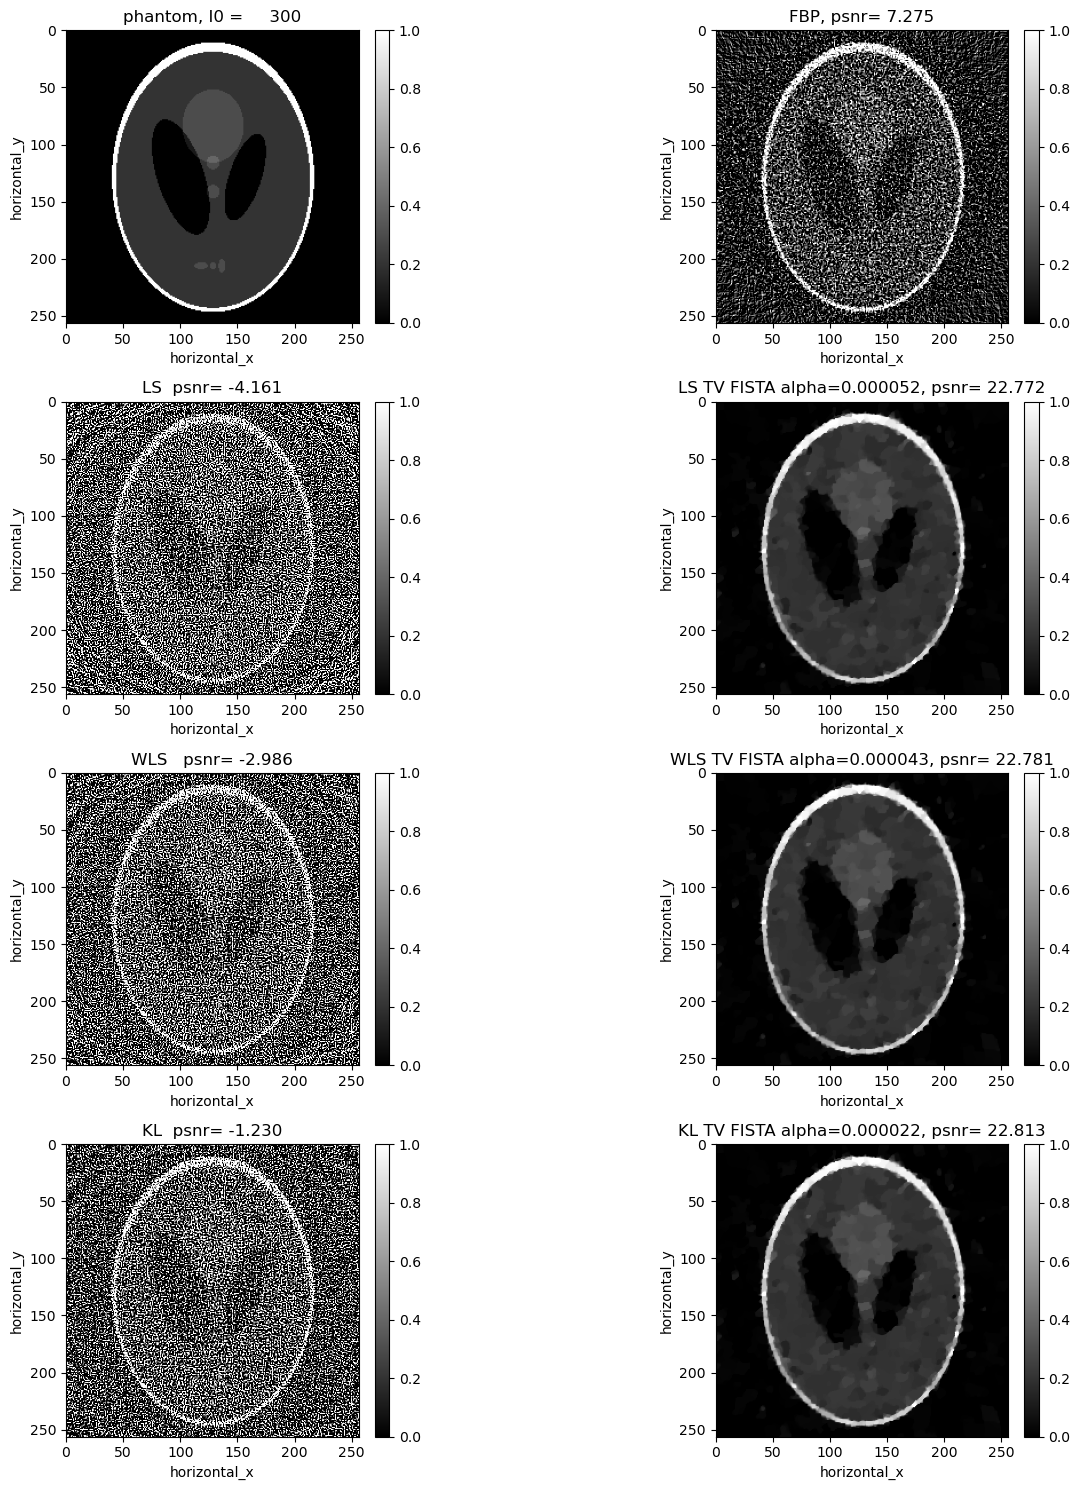

Comparisons without regularisation#

show2D([phantom, recon_fbp, recon_ls,recon_wls, recon_kl ], ["phantom, I0 = %7.0f" % (background_counts), "FBP, psnr= %5.3f" % (psnr_fbp),\ "LS psnr= %5.3f" % (psnr_ls),\ "WLS psnr= %5.3f" % (psnr_wls), \ "KL psnr= %5.3f" % (psnr_kl)], \ cmap=cmap, fix_range =(0,1), num_cols=3, origin='upper-left')

The KL reconstruction is better than the WLS reconstruction which is better than the LS reconstruction. However, all the above reconstructions are worse than the FDK reconcstruction and seem to be overfitting to the noise. In the next section, we consider reconstructions with TV regularisation.

Reconstructing the noisy data using least squares with Total Variation regualrisation#

In addition to the least-square term, we considered a Total Variation Regulariser. So, for the LS-TV problem, we want to minimize the following:

\[||Y-Ax||_{2}^{2} + \alpha \, TV(x)\]

where \(\alpha\) is the regularization parameter that balances the two terms. In the next box, we search over a range of values of \(\alpha\) to find the best one for our data.

Similar to the least squares cas, in addition to the weighted least square term, we considered a Total Variation Regulariser. We minimize:

\[||Y-Ax||_{W}^{2} + \alpha \, TV(x)\]

where \(\alpha\) is the regularization parameter that balances the two terms. Again we search a range of values of \(\alpha\) to find the best one for the data.

Reconstructing the noisy data using KL divergence with TV regularisation#

As in the least squares and weighted least squares case, we add in a TV regularisation term and search for an optimal regularisation parameter.

Comparisons with TV#

show2D([phantom, recon_fbp, recon_ls_tv_fista,recon_wls_tv_fista, recon_kl_tv_fista ], ["phantom, I0 = %7.0f" % (background_counts), "FBP, psnr= %5.3f" % (psnr_fbp),\ "LS TV FISTA alpha=%7.6f, psnr= %5.3f" % (alpha_ls_tv_fista,psnr_ls_tv_fista),\ "WLS TV FISTA alpha=%7.6f, psnr= %5.3f" % (alpha_wls_tv_fista,psnr_wls_tv_fista), \ "KL TV FISTA alpha=%7.6f, psnr= %5.3f" % (alpha_kl_tv_fista,psnr_kl_tv_fista)], \ cmap=cmap, fix_range =(0,1), num_cols=3, origin='upper-left')

Compare all the reconstructions#

show2D([phantom, recon_fbp, recon_ls, recon_wls_tv_fista, recon_wls, recon_wls_tv_fista,  recon_kl, recon_kl_tv_fista ], ["phantom, I0 = %7.0f" % (background_counts), "FBP, psnr= %5.3f" % (psnr_fbp),\

"LS  psnr= %5.3f" % (psnr_ls), "LS TV FISTA alpha=%7.6f, psnr= %5.3f" % (alpha_ls_tv_fista,psnr_ls_tv_fista), \

"WLS   psnr= %5.3f" % (psnr_wls),  "WLS TV FISTA alpha=%7.6f, psnr= %5.3f" % (alpha_wls_tv_fista,psnr_wls_tv_fista), \

"KL  psnr= %5.3f" % (psnr_kl),    "KL TV FISTA alpha=%7.6f, psnr= %5.3f" % (alpha_kl_tv_fista,psnr_kl_tv_fista)], \

cmap=cmap, fix_range =(0,1), num_cols=2, origin='upper-left')